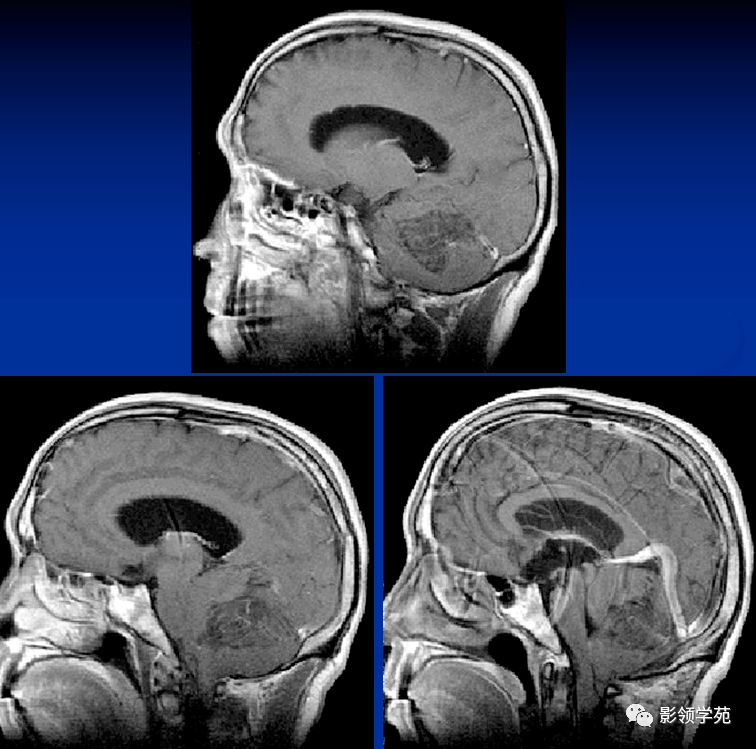

正常小儿颅脑的磁共振表现